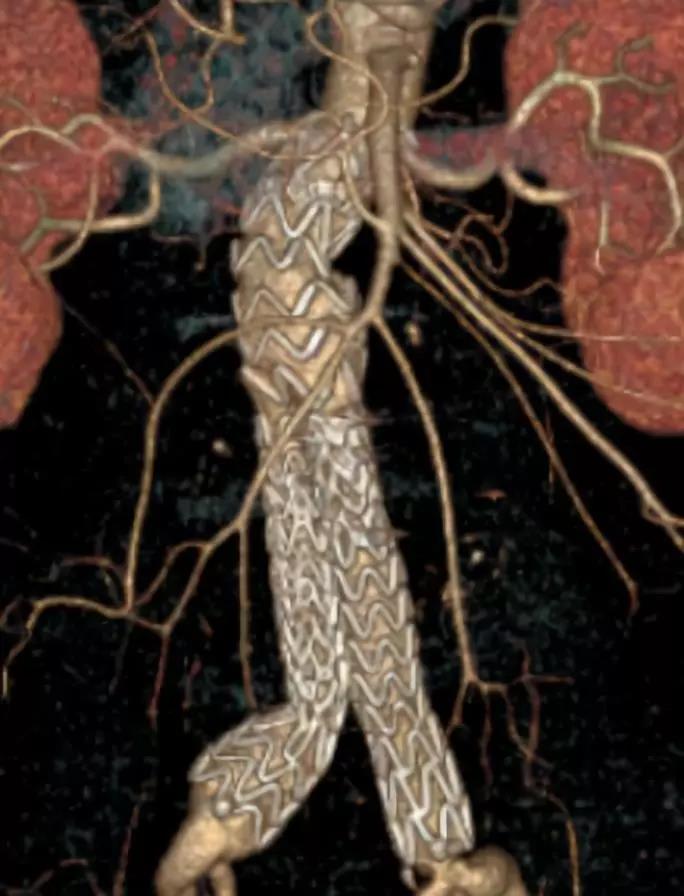

此次研究,纳入腹主动脉瘤的最大直径为85mm,平均直径为50.78mm;最短瘤颈长度为11mm,平均长度为31.34mm;最大肾下成角为74.6度,平均角度为32.48度。从动脉瘤最大直径变化来看,经过腹主动脉腔内治疗后,在出院前和术后6个月都有所减小。 在此次研究中,先健Yuranos™新一代腹主动脉覆膜支架系统临床试验初步展现了优秀的临床试验结果,其30天内MAE发生率低,安全性得以验证;而且由于该产品的柔顺性有较大提升,输送器直径减小,对于短瘤颈和角度大的病例是更好的选择。 入组病例展示: 病例一:男性,年龄69岁,既往高血压,糖尿病病史。术前腹主动脉瘤直径67.3mm,近端瘤颈长度23.2mm,近端锚定区直径21.2mm,肾下成角60.5度。 术中从右侧股动脉穿刺,选用先健型号为AB-2412-50-120的主体支架,支架近端定位于右肾动脉开口处,后释放打开裸支架,并向下释放主体短分支,左侧输送进入先健髂动脉延长支架IE-1416-100,并释放,保留左侧髂内动脉。接着释放主体长分支,右侧输送进入先健髂动脉延长支架IE-1424-80,并释放,保留右侧髂内动脉。 手术顺利,无内漏,持续时间1小时10分钟。术后CTA检查,支架形态良好,无内漏。详见下图: 术前影像 术中影像 出院前影像 术后6个月影像 术后1年影像 病例二:女性,年龄72岁,既往高血压,静脉曲张病史。术前腹主动脉瘤直径48.81mm,近端瘤颈长度16.15mm,近端锚定区直径18.43mm,肾下成角66度。 术中从右侧股动脉穿刺,选用先健型号为AB-2412-50-140的主体支架,支架近端定位于右肾动脉开口处,后释放打开裸支架,并向下释放主体短分支,左侧输送进入先健髂动脉延长支架IE-1414-120,并释放,保留左侧髂内动脉。接着释放主体长分支,右侧输送进入先健髂动脉延长支架IE-1414-80,并释放,保留右侧髂内动脉。